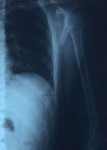

mi última adquisición son dos costillas rotas.

Attached Files:

que te recuperes pronto franci.

Animo y recuperate pronto de esas "heridas de guerra"

Gracias, ya llevo 38 días y me encuentro mejor, yo calculo que para vacaciones de navidad daré mi primera vueltecita.